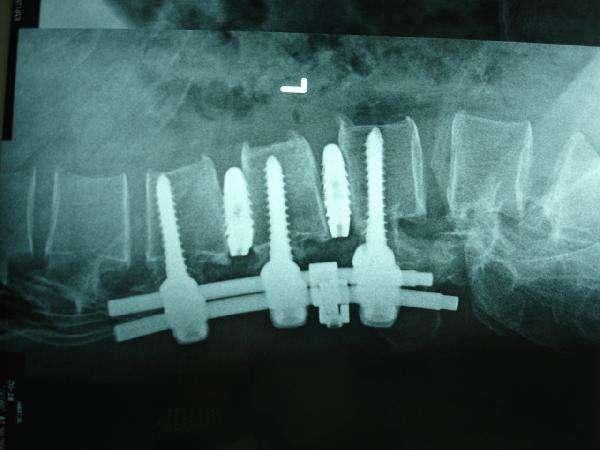

- La chirurgie est également envisagée pour les patients qui ont une longue histoire avec la maladie et dont les symptômes ne sont pas soulagés par les traitements conservateurs. En fonction de l'état du patient, il existe différentes options de chirurgie mini-invasive et de chirurgie générale.

Hernie discale lombaire : au stade précoce de la maladie, un traitement conservateur peut être utilisé lorsque les symptômes généraux ne sont pas évidents. Avec l'évolution de la maladie, lorsque les symptômes sont plus graves et que le traitement conservateur est inefficace, une intervention chirurgicale peut être envisagée.